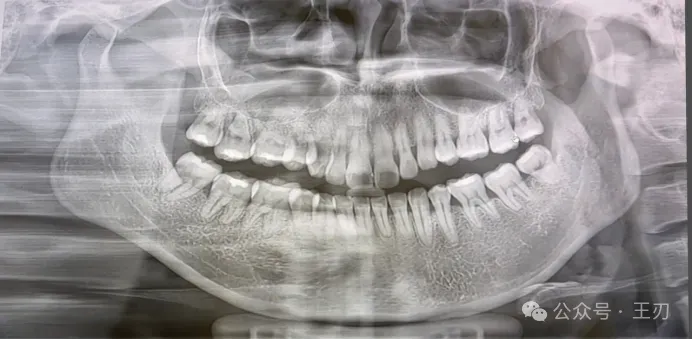

这是患者的X线全景片,是她三个月前洗牙的时候医生帮她拍的,该医生从这张全景片判断她没有牙周炎,尽管她要求了探诊,但医生拒绝探诊,并告知她“应该没有牙周炎”。

这是该医生给她照的全口咬合翼片,从该组片子上也没有发现特别明显的牙槽骨吸收,所以该位医生再次确认自己的判断–患者没有牙周炎。